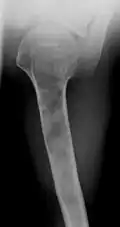

X-ray showing enchondromas localized in the humerus of a 37-year-old patient affected with Ollier disease -

X-ray showing enchondromas localized in the lower part of the radius of a 37-year-old patient affected with Ollier disease -